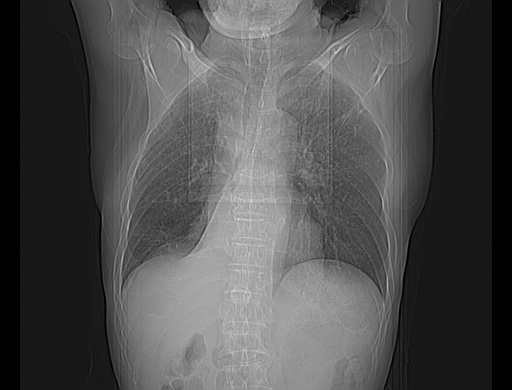

男性患者,63岁。右侧胸背部疼痛2月,加重一周。

考虑:右肺中央型肺癌并右肺下叶不张;两肺尖继发性肺结核。

还有纵隔多处肿大淋巴结及肋骨的改变、两肺多发结节灶。

考虑右中心型肺癌并右下肺不张,肺及纵隔,左肋骨转移。

右肺下叶中心性肺癌并纵隔淋巴结转移,左侧肋骨转移。双肺上叶继发性结核表现。

1)右肺下叶中心性肺癌并纵隔淋巴结转移,两肺转移,左侧肋骨转移。2)双肺上叶继发性结核。

右肺下叶中心性肺癌并纵隔淋巴结及两肺、左侧肋骨转移。双肺上叶继发性结核表现。